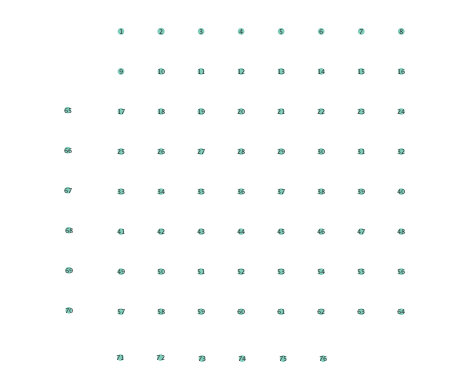

In order to assess the information-routing abilities of brain regions before and after seizure onset, comparisons of the so-termed betweenness centrality were done. Betweenness centrality of a node computes the fraction of shortest paths between all node pairs that traverse the given node, and it is useful to identify the key information transmitting hubs in a network; see e.g., [24] for more details. The per-node betweenness centrality for each inferred network are depicted in Figure 4, with node radii similarly encoding the computed values. Little variation between preictal and ictal betweenness centralities is seen for the linear model (Figures 4 (a) and (b)), while variations are slightly more marked for the K-SVARM, see Figures 4 (c) and (d). It can be seen that modeling nonlinearities reveals subtle changes in information-routing capabilities of nodes between preictal and ictal phases.